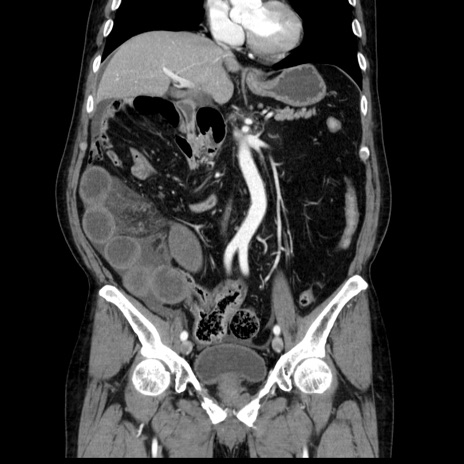

症例30(冠状断像)

【症例】80歳代男性

【主訴】臍周囲痛

【現病歴】約6時間前から臍下部痛が出現。次第に腹部膨隆・背部痛も生じてきたため来院。背部痛の場所は変化しない。

【身体所見】意識清明、BT 36.3℃、BP  131/87mmHg、P 87bpm、SpO2 100%(RA)、臍周囲自発痛・圧痛あり、反跳痛なし、自発痛部位に一致して板状硬あり、腹部膨隆、腸雑音減弱、CVA tenderness両側陰性。

【データ】WBC 19600、CRP 0.33